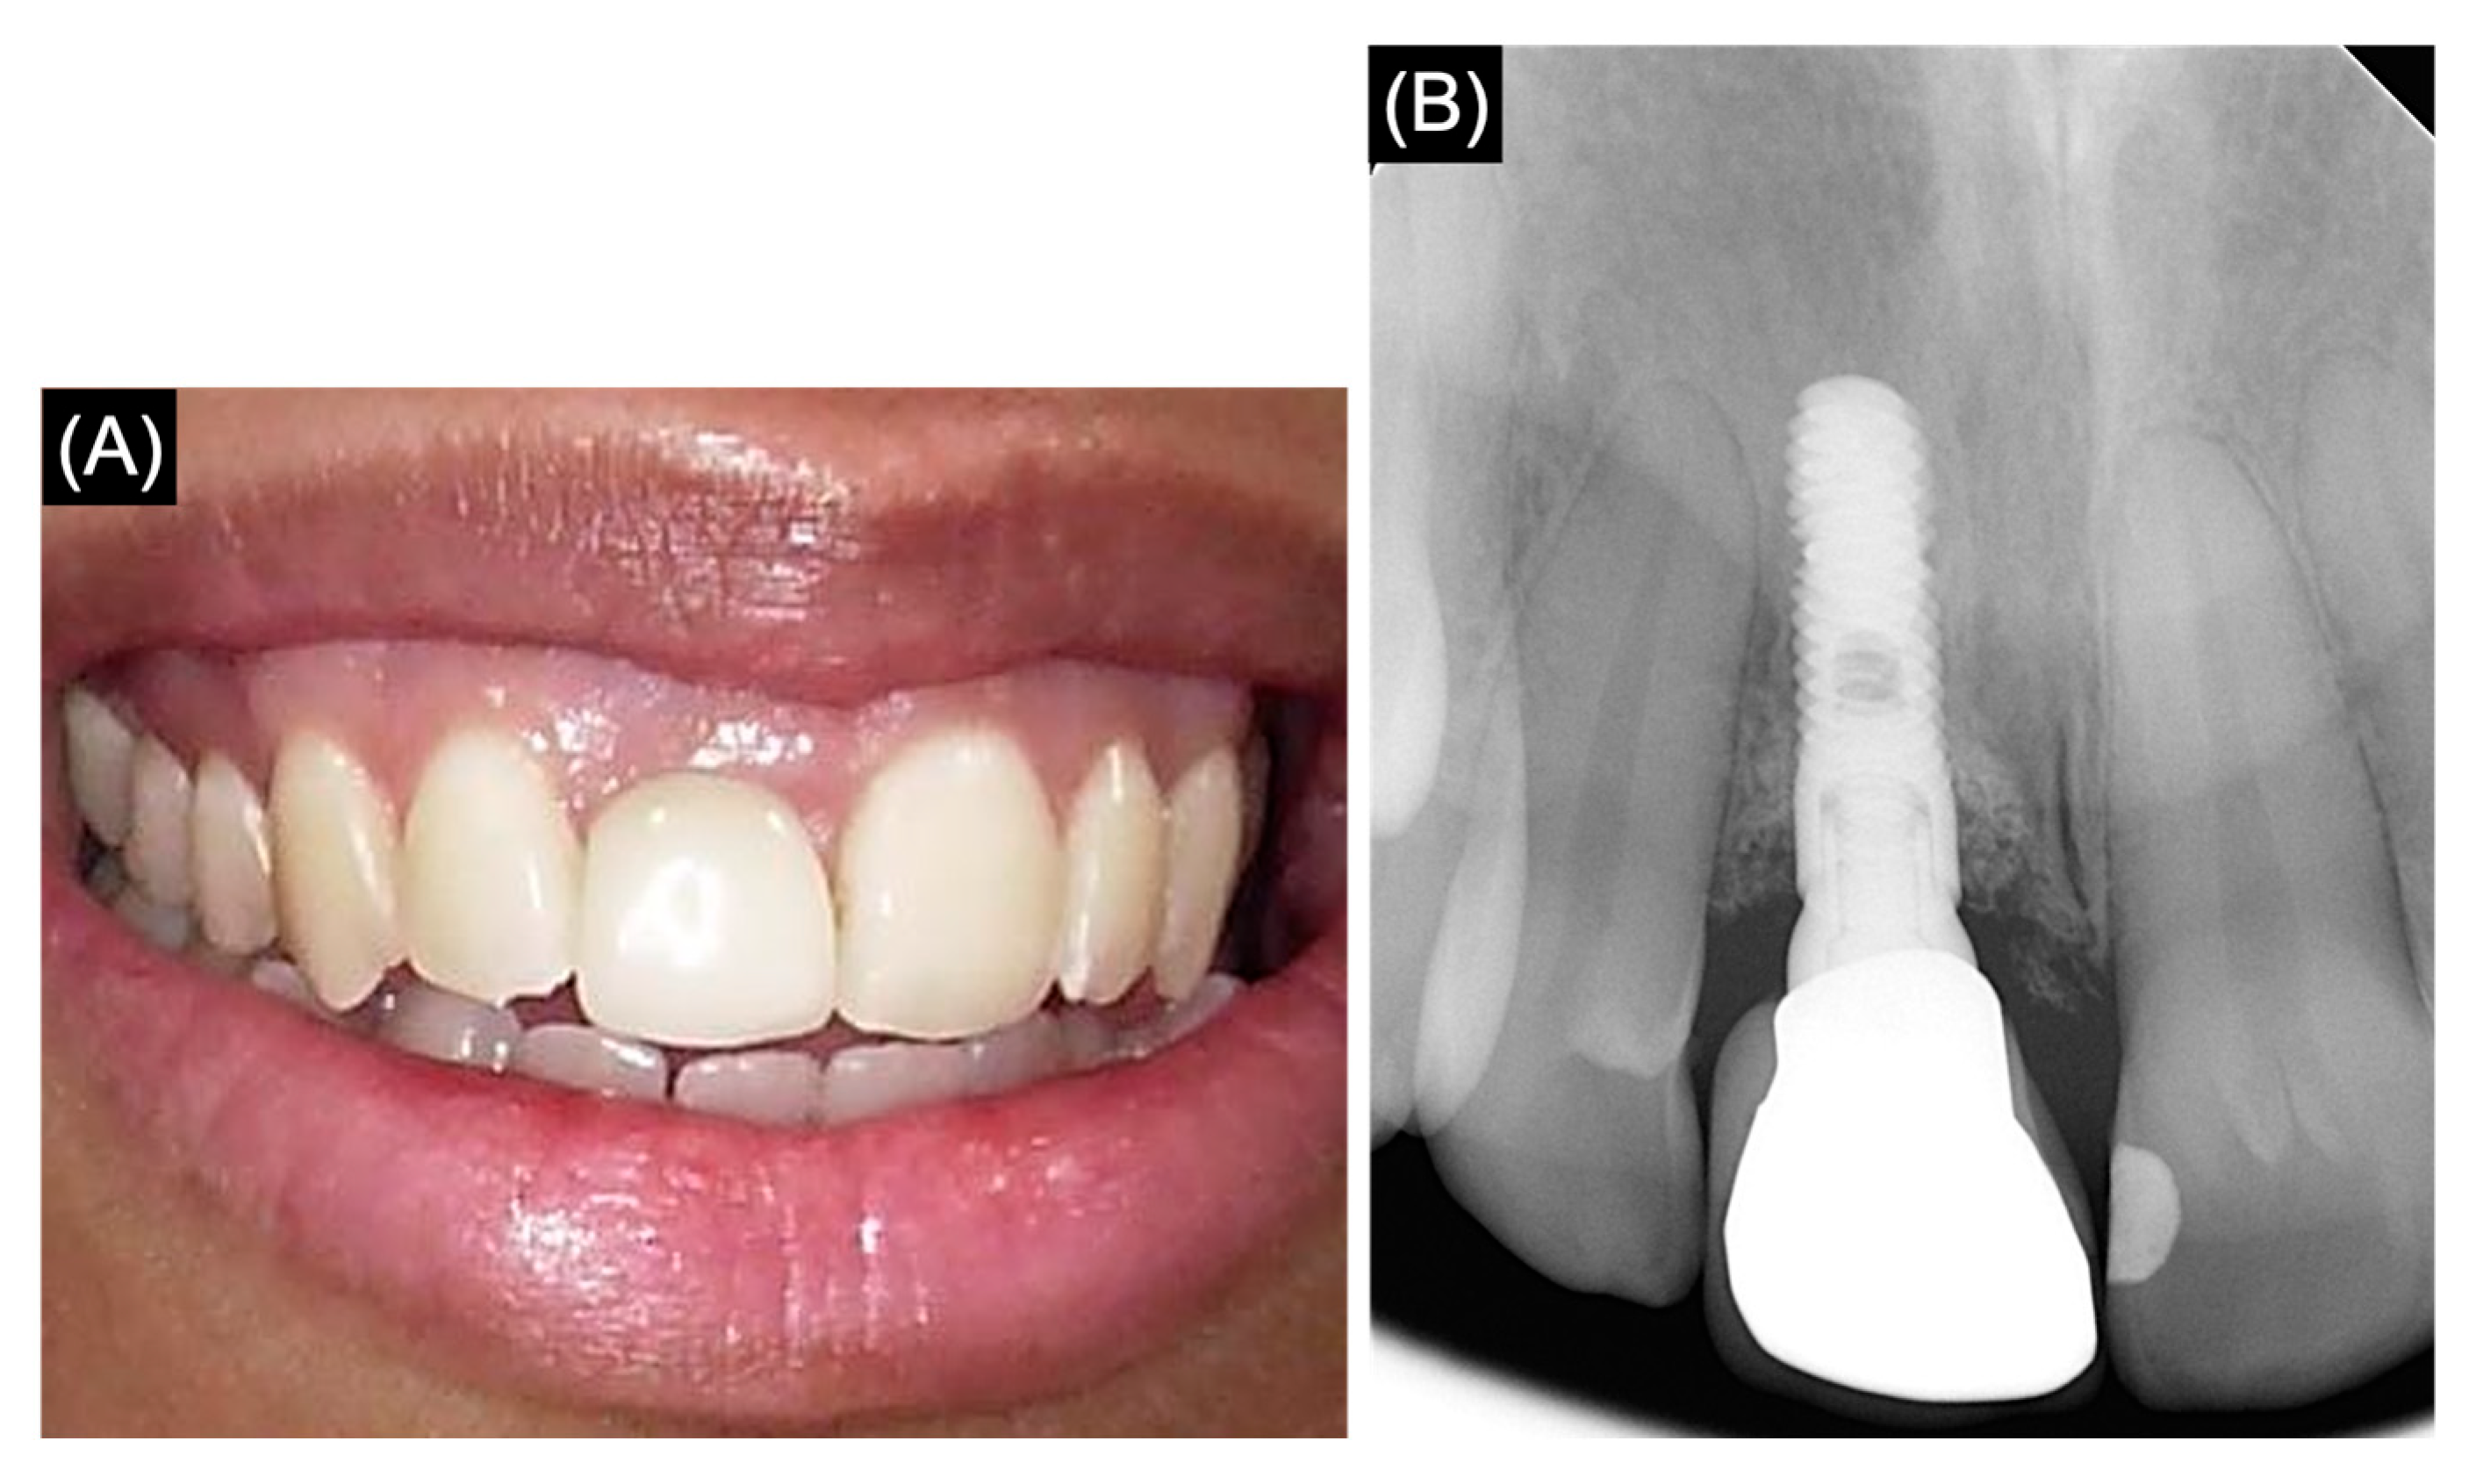

2.3. Follow-Up Visit